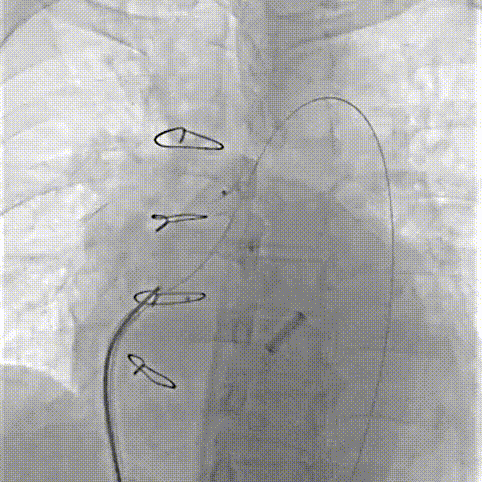

术中操作

2.Aortic Wrapping吻合口漏位置多有不同,常见的是冠脉吻合口位置和升主动脉人工血管与自体远端血管吻合口位置,少数患者合并人工瓣膜瓣周漏。因此,此类手术是典型的不定型手术,特别是对于拟行微创封堵手术患者,术前多模态影像评估,尤其是3D打印实物模型对于手术方案制定有重要意义。

4.对于Aortic Wrapping吻合口漏,应优选入口出口双伞封堵,有利于术后包裹腔快速机化消除分流。